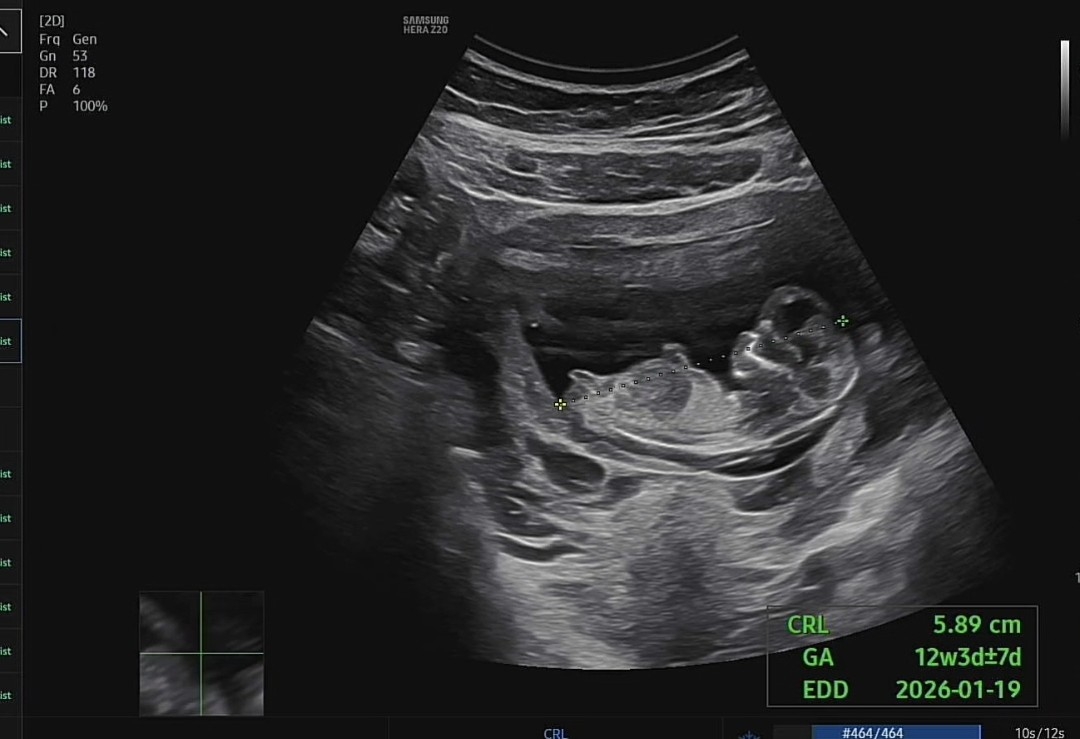

각도법봐주세요

딸? 아들? 뭘까요ㅠㅠ